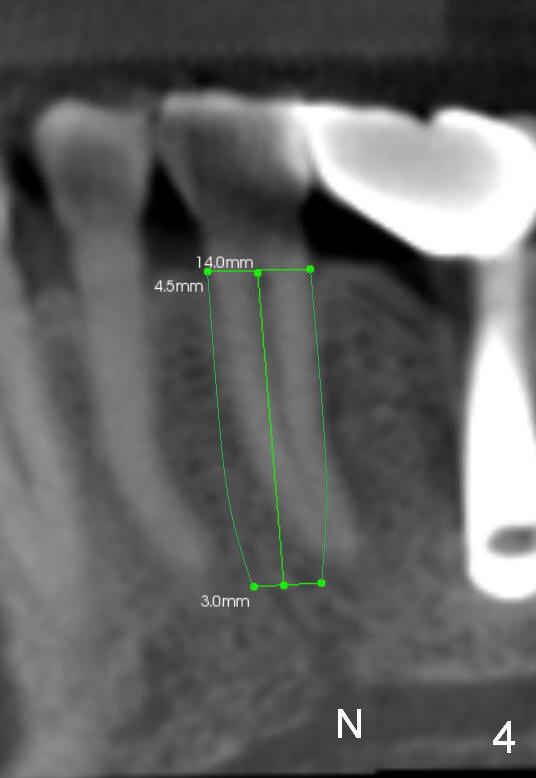

CT sagittal section of a similar case shows that the root is also long, but curved (Fig.4).  A 4.5x14 mm implant is slightly longer than the root.  The apex of the implant has distance to the underlying nerve (N).  The coronal section shows that the implant should be placed lingually (Fig.5 L), since the buccal (B) plate is thin (Fig.6 between arrowheads).  The first drill (2 mm) is to be placed lingually (Fig.7 red arrow).  When the implant is placed, there should be a buccal gap, to be filled with bone graft (Fig.5 red circles).